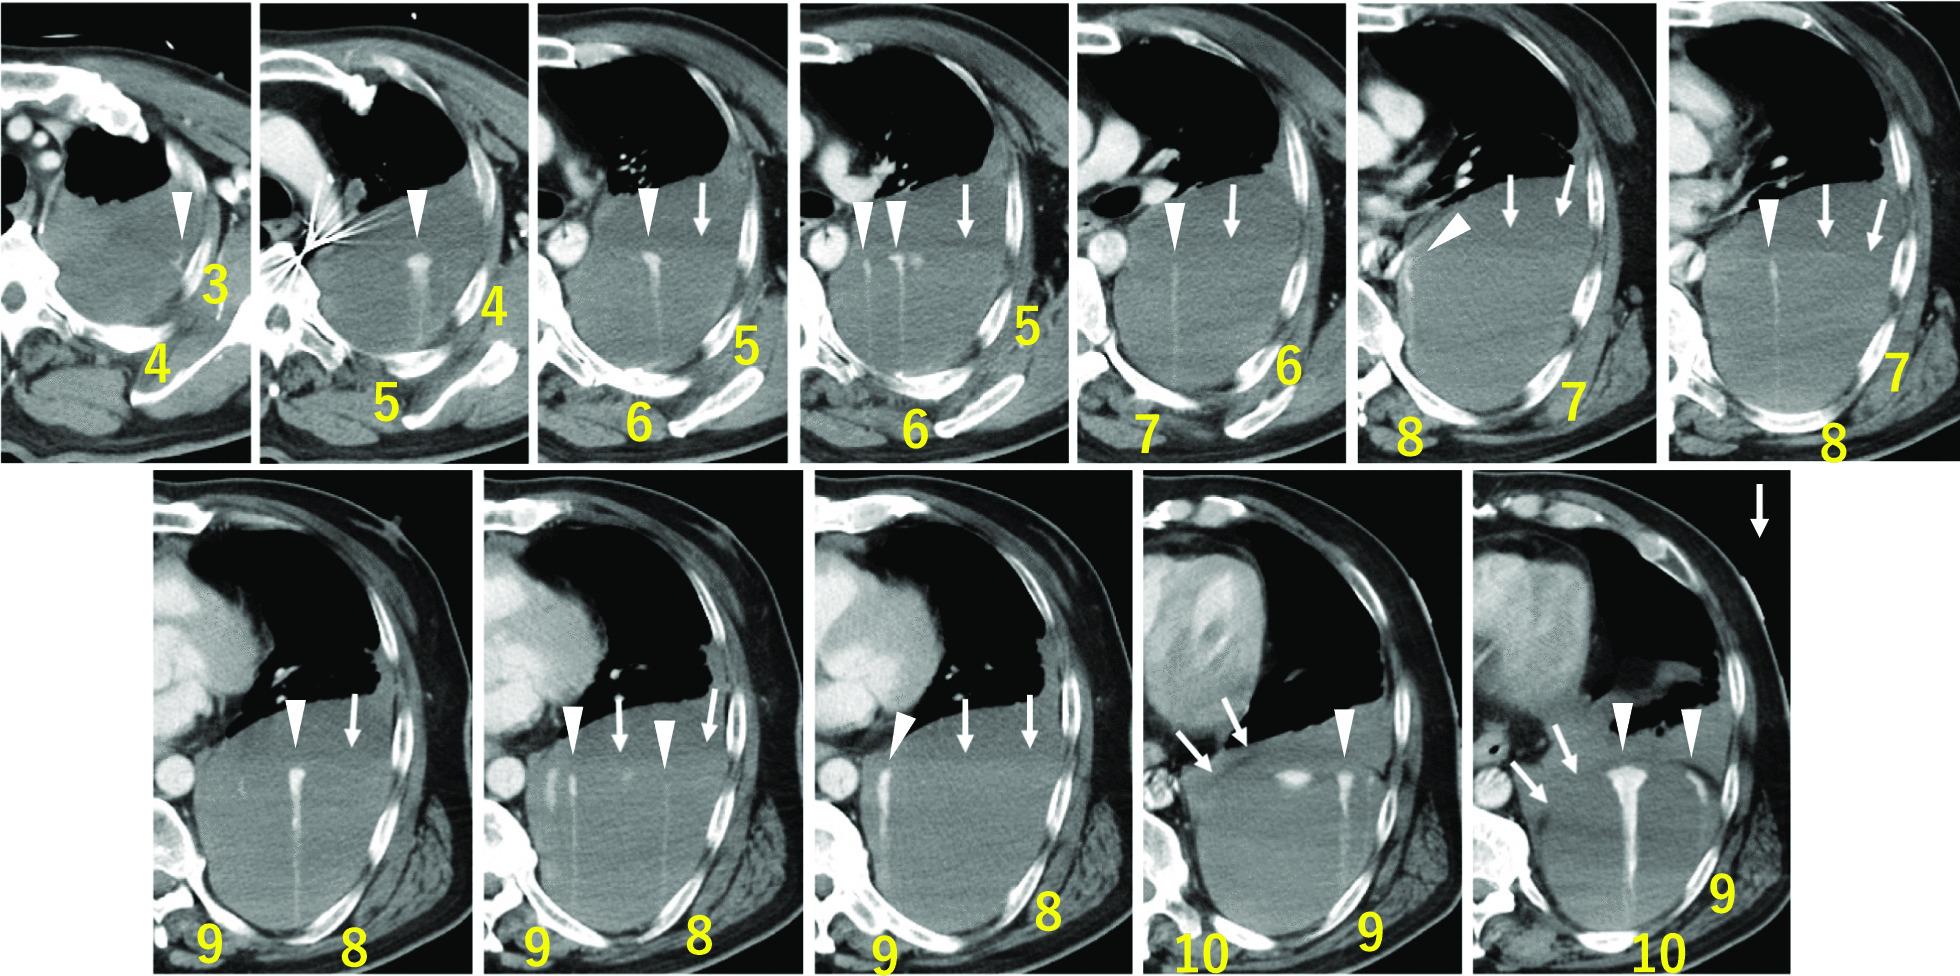

A 63-year-old Japanese man was admitted to the emergency department owing to sudden chest and back pain, dizziness, and nausea. Emergency coronary angiography revealed myocardial infarction secondary to right coronary artery occlusion. After intra-aortic balloon pumping, percutaneous coronary intervention was performed in the right coronary artery. At 12 hours following percutaneous coronary intervention, the patient developed new-onset left anterior chest pain and hypotension. Contrast-enhanced computed tomography revealed 15 sites of contrast extravasation within a massive left extrapleural hematoma. Emergency angiography revealed contrast leakage in the left 6th to 11th intercostal arteries; hence, transcatheter arterial embolization was performed. At 2 days after transcatheter arterial embolization, his blood pressure subsequently decreased, and contrast-enhanced computed tomography revealed the re-enlargement of extrapleural hematoma with multiple sites of contrast extravasation. Emergency surgery was performed owing to persistent bleeding. No active arterial hemorrhage was observed intraoperatively. Bleeding was observed in various areas of the chest wall, and an oxidized cellulose membrane was applied following ablation and hemostasis. The postoperative course was uneventful.

一名 63 岁的日本男性因突发胸痛、背痛、头晕和恶心而被收入急诊部。紧急冠状动脉造影显示右冠状动脉闭塞引起的心肌梗死。在主动脉内球囊泵后,对右冠状动脉进行了经皮冠状动脉介入治疗。在经皮冠状动脉介入治疗后 12 小时,患者出现新发左前胸疼痛和低血压。增强 CT 显示巨大左胸外血肿内有 15 个造影剂外渗部位。紧急血管造影显示左第 6 至 11 肋间动脉有造影剂渗漏;因此,进行了经导管动脉栓塞术。在经导管动脉栓塞术后 2 天,他的血压随后下降,增强 CT 显示胸外血肿再次扩大,有多个造影剂外渗部位。由于持续出血,进行了紧急手术。术中未观察到活跃的动脉出血。在胸腔壁的各个部位观察到出血,并在消融和止血后应用氧化纤维素膜。术后过程平稳。